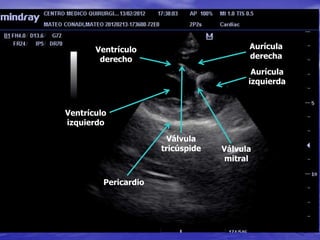

ECOCARDIOGRAFIA

Aorta

Ventrículo

derecho

Aurícula

izquierda

Pericardio

izquierdo

derecha

Válvula

tricúspide Válvula

mitral